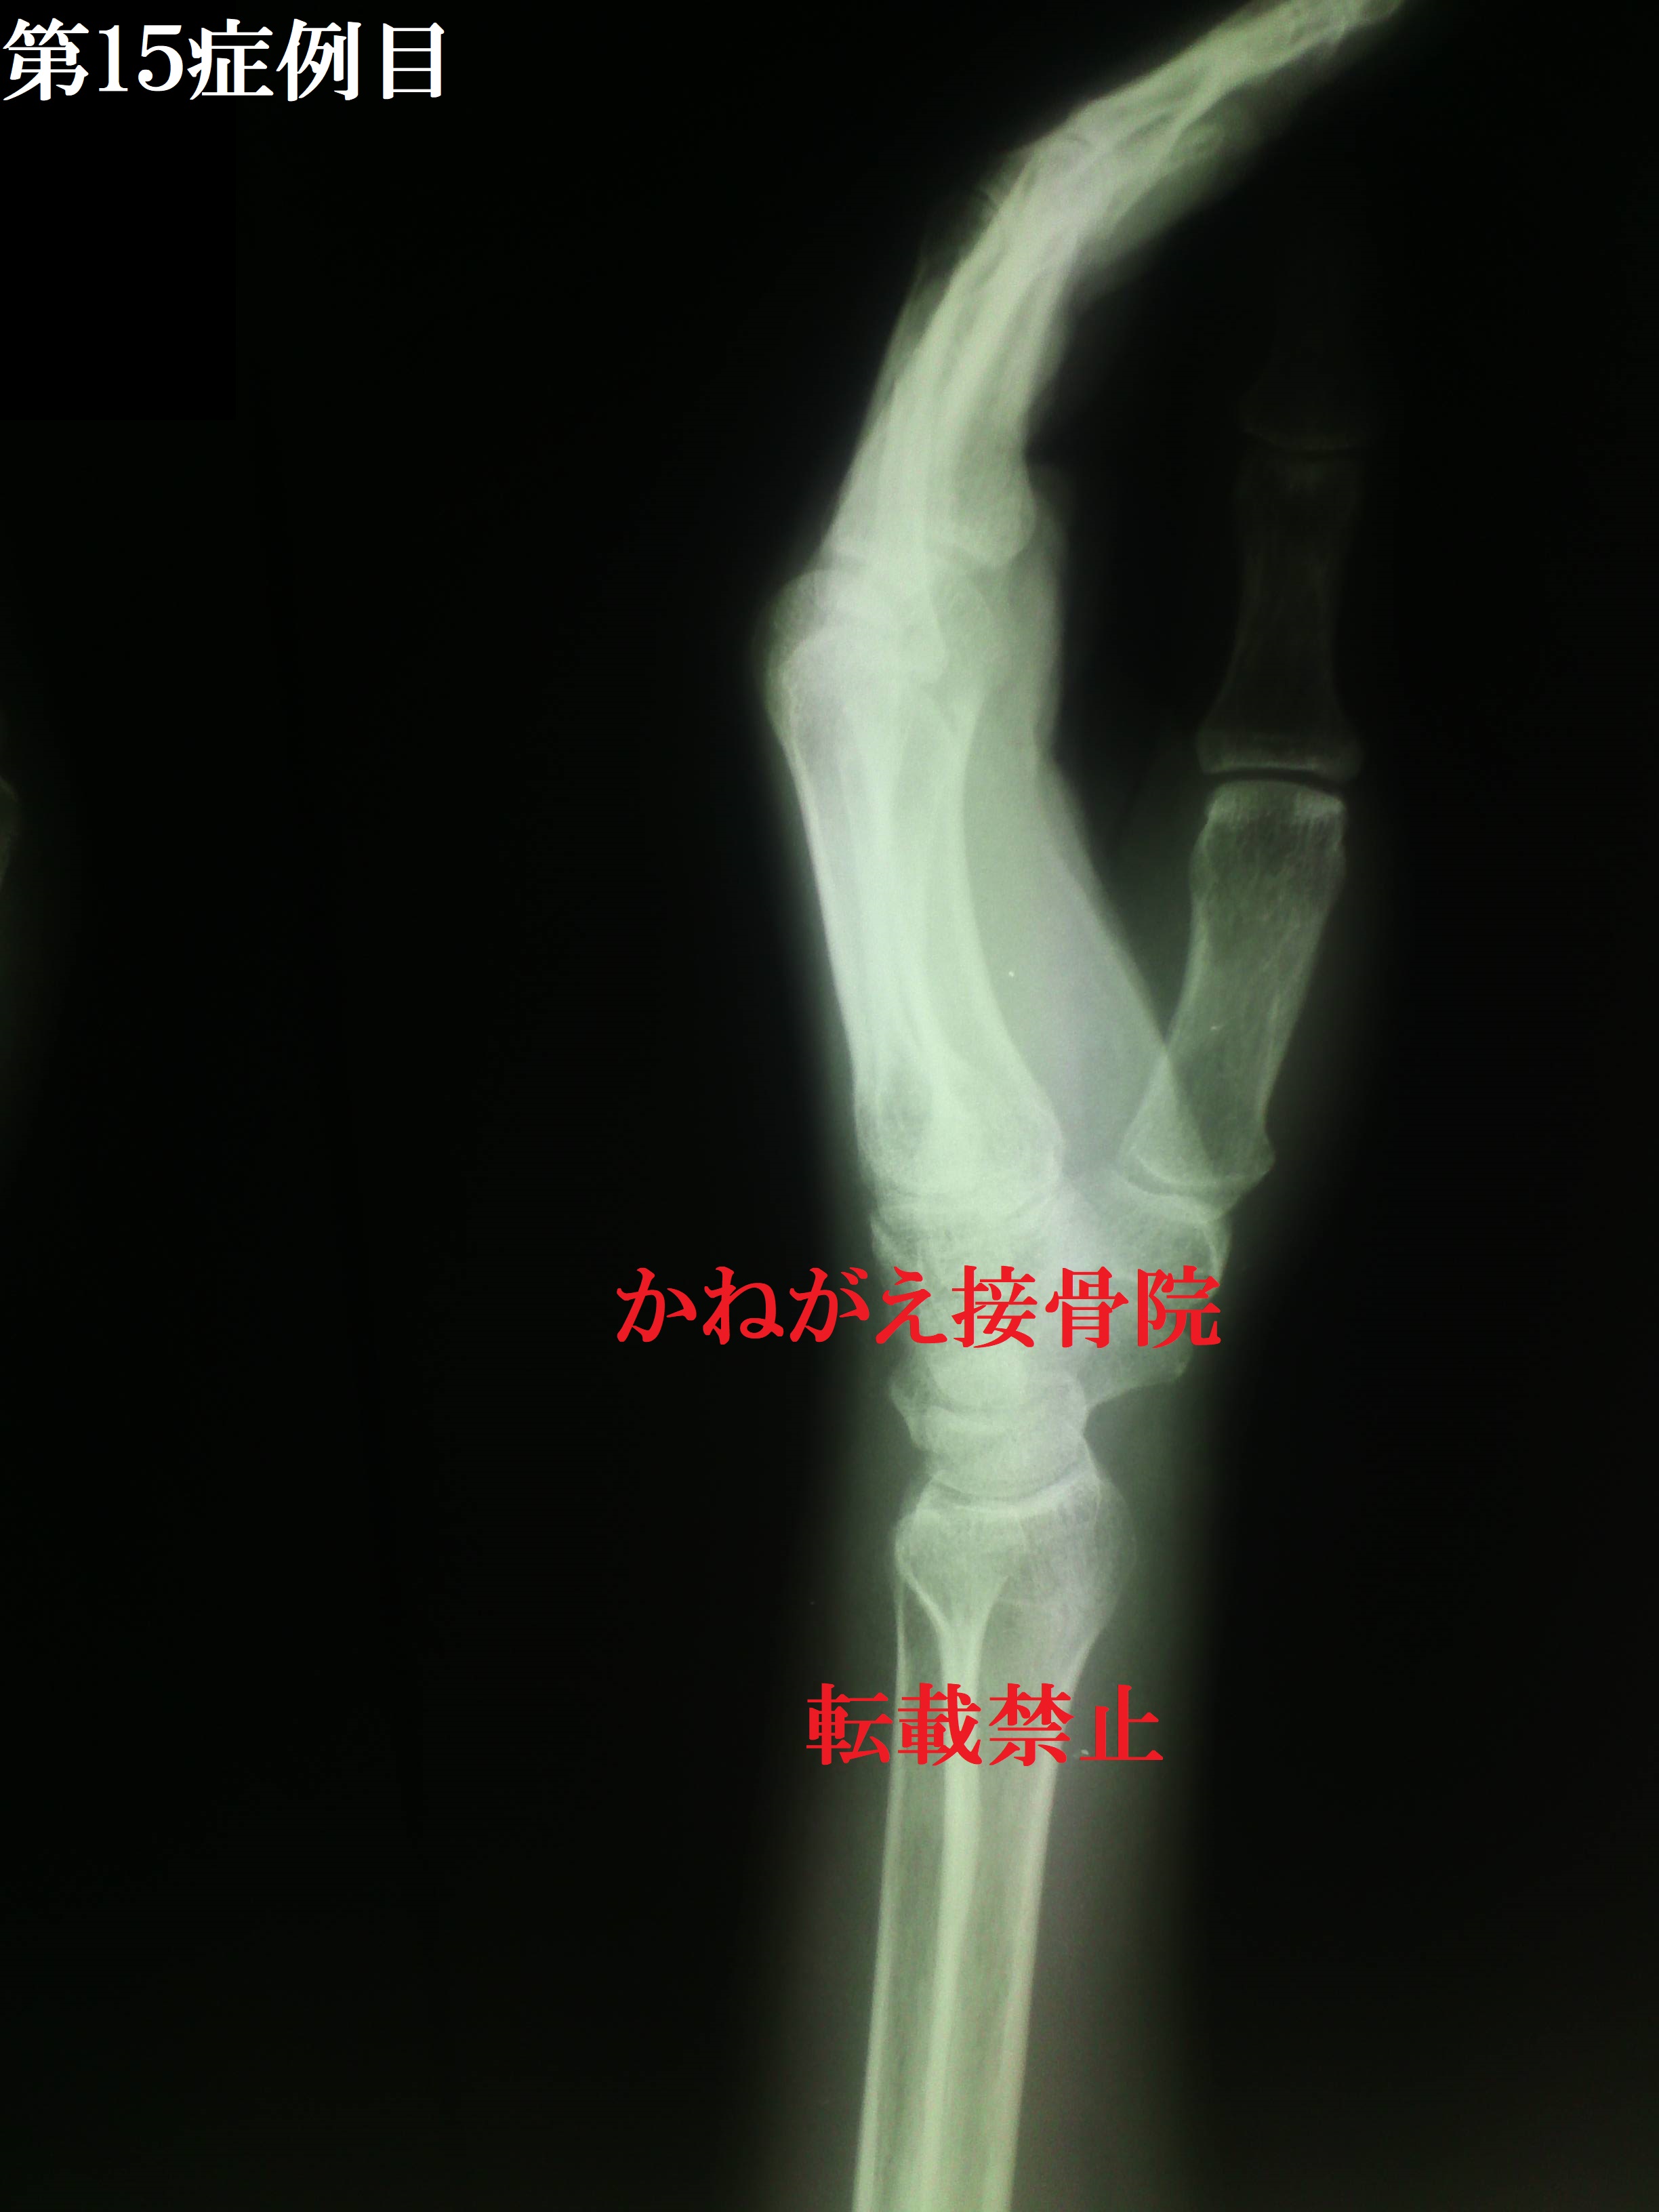

結果から言うと、「Repo perfect」 でした。 しっかり橈骨が伸びていて、背屈もとれています ね。 この患者さんは整復の時に失神しそうになったの ですが、リハビリのROM訓練では非常に痛みに 強くてびっくりしたのを覚えています。 治療期間も4か月程で完治されました。 皆さんもお酒に限らず、転倒するキッカケはたく さん潜んでいますので気をつけてください。 そして万が一転んで痛めたときは遠慮なくご相談 ください。 以上、第15症例目の整復レポートでした。